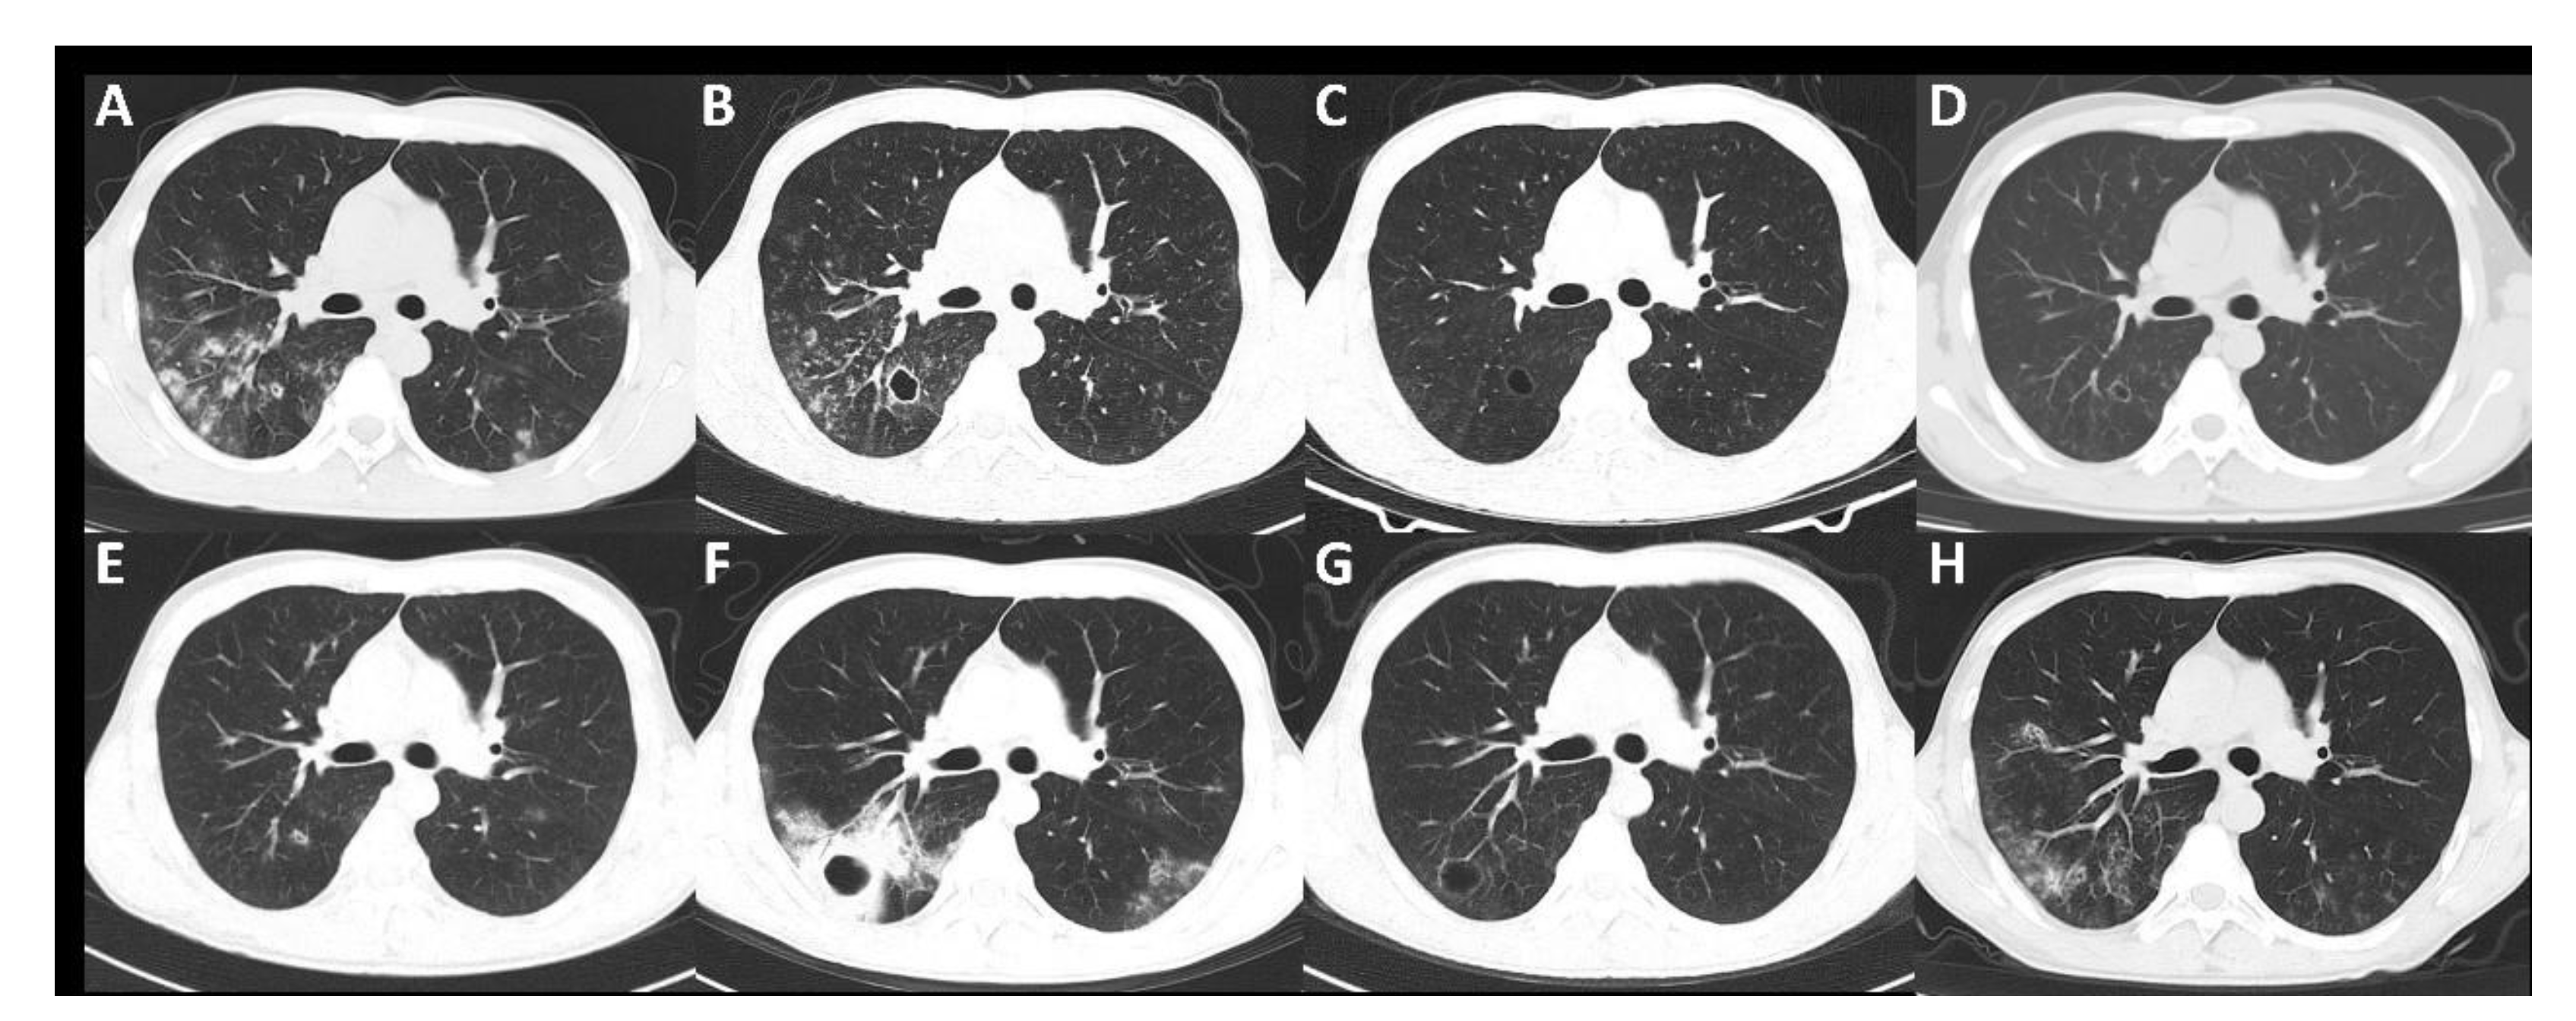

Changes in chest CT imaging, SCr, 24 h urine protein (24 h-UP) and the treatment of the patient are summarized in Figure 2 and Figure 3. The patient underwent four bronchoalveolar lavage fluid (BALF) cultures in November 2018, April 2019, November 2019 and April 2021, revealing persistent positive Pseudomonas aeruginosa and positive benzoxicillin-sensitive Staphylococcus aureus twice (November 2018 and November 2019).

On the basis of careful review of chest imaging, SCr, 24 h-UP and the treatment of the patient, we found that the improvement in chest imaging findings was always related to antibiotic treatment, whereas immunosuppressive therapy did not lead to improvement. In April 2019 in particular, in the course of treatment with sufficient glucocorticoids and cyclophosphamide, the decreased 24 h-UP showed a significant rebound.

Figure 2. Changes in chest CT imaging during treatment. (A) In October 2018, before anti-tuberculosis treatment, patchy shadows were seen in the posterior segment of the right upper lobe and the dorsal segment of the left lower lobe. (B) In December 2018, after 3 months of anti-tuberculosis treatment. A new cavity appeared in the lower lobe of the right lung. (C) In February 2019, after receiving levofloxacin, glucocorticoids and cyclophosphamide for one month, the multiple patchy shadows in both lungs were alleviated, and the right pulmonary cavity was reduced, with a thinner wall. (D) In April 2019, after receiving glucocorticoids and cyclophosphamide for 3 months, there were more patchy shadows in both lungs, and the right pulmonary cavity was smaller, but the cavity wall was thicker. (E) In May 2019, after receiving ceftazidime treatment, the right lung cavity shrank. (F) In November 2019, after receiving glucocorticoid and azathioprine therapy for 4 months, new-onset patchy consolidation in both lungs was observed. A thick-walled cavity appeared in the right lower lung. (G) In November 2019, after receiving meropenem, cefepime and moxifloxacin treatment, the lesions in both lungs were significantly reduced, and the cavity wall of the right lower lobe became thinner. (H), In March 2021, after receiving prednisone, azathioprine and mycophenolate mofetil, multiple patches and nodular shadows in both lungs, some of which showed cavitation, were observed.